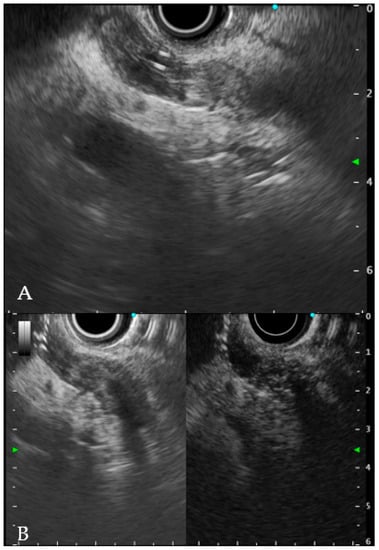

6.2. Endoscopic Ultrasound

6.3. Tissue Is the Real Issue